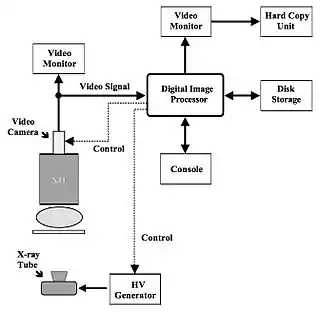

- Figure 7.5 shows a block diagram of an imaging system used for DSA which is based on XII-video technology. It is seen that images from the video camera are fed to a digital image processor for manipulation, storage and display. In order to implement a pulsed exposure mode of operation, control connections are required between the image processor and both the video camera and the HV generator. These control connections are used to instruct the HV generator to initiate each exposure pulse and to select the appropriate mode of operation of the video camera. Systems frequently include a variable optical aperture between the XII and the video camera. Note that this device is not included in the figure for reasons of clarity.

- The intense radiation exposures used for pulsed exposure DSA generate relatively bright images at the XII output. Since such bright XII images are likely to saturate the video camera (which typically has a high sensitivity to light), the optical aperture is generally used to control the illumination of the target of the video camera. The aperture is set wide when fluoroscopic exposures are used for patient positioning purposes and narrowed during the DSA exposures. The exact setting of the aperture is dependent on the particular examination and is generally set automatically by the digital image processor.

- High power X-ray generators and XRTs are required for DSA. Hence, generators are used which, for instance, can produce exposures up to 100 kV, 1000 mA with very short exposure times and XRTs are used which are of high heat capacity and small focal spots, e.g. 0.5 mm. The generator should also be capable of generating low, continuous exposures for catheter guidance and patient positioning purposes.